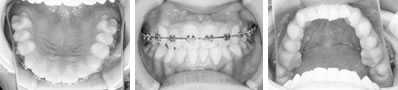

片顎のマルチブラケットで改善した9歳症例

前歯部分の凸凹は上下とも重度であった。乳歯の虫歯も多く、歯磨き練習も重要でした。

右上の2番を1本だけ抜歯しました